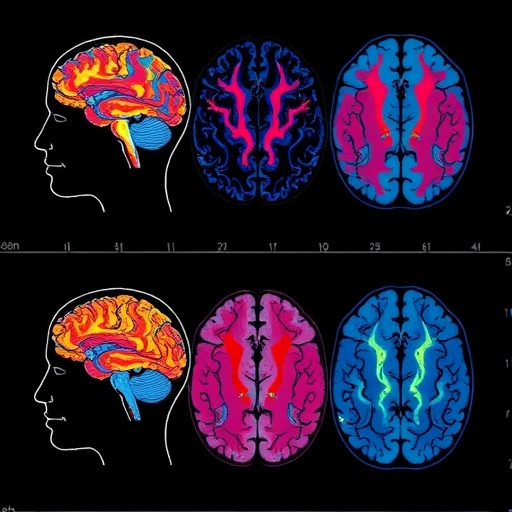

Regional homogeneity (ReHo) is a metric derived from resting-state functional magnetic resonance imaging (fMRI), reflecting the temporal consistency of neural activity among neighboring voxels. In healthy individuals, certain brain areas exhibit highly synchronized activity patterns, indicative of functional integration essential for mood regulation and cognition. Disruptions in ReHo can signify aberrant regional interactions contributing to depressive symptomatology. By establishing normative reference models from large-scale neuroimaging datasets, the researchers could pinpoint how individual patients with MDD deviate from typical ReHo patterns, revealing unique neurophenotypic signatures.

Strikingly, the normative model approach revealed that not all depressed individuals share the same neural disturbances. Some exhibited pronounced hypo-synchrony in fronto-limbic circuits, regions implicated in emotion processing and regulation, whereas others showed hyper-synchrony in default mode network areas often linked to rumination and self-referential thought. These divergent patterns underscore the need to reconceptualize MDD beyond symptomatic descriptions toward neurobiologically grounded classifications.